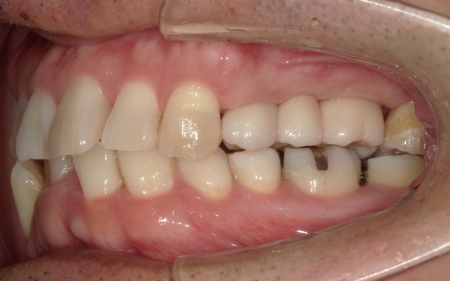

患者様は「可能な限り自分の歯を残したい」と希望されており、長期的な安定と清掃のしやすさを考慮して、②のインプラントブリッジによる治療を選択されました。

インプラントがしっかりと骨に定着したことを確認したら、精密な型取りを行い、ブリッジを作製して装着しました。

インプラント治療と併せて保存可能な歯の治療も進め、右上の一番奥の歯と右下の奥歯(前から5番目と6番目)に対して、細菌感染した神経を取り除いてから薬を詰める根管治療を行い、CAD/CAM冠という白い被せ物で修復しました。

さらに、上前歯(右上の犬歯から左上の犬歯まで)、右下の4番目の歯に対しては、虫歯治療を行っています。

最後に、痛みや違和感がないか、見た目や噛み合わせに問題がないかを確認し、治療を終了しました。